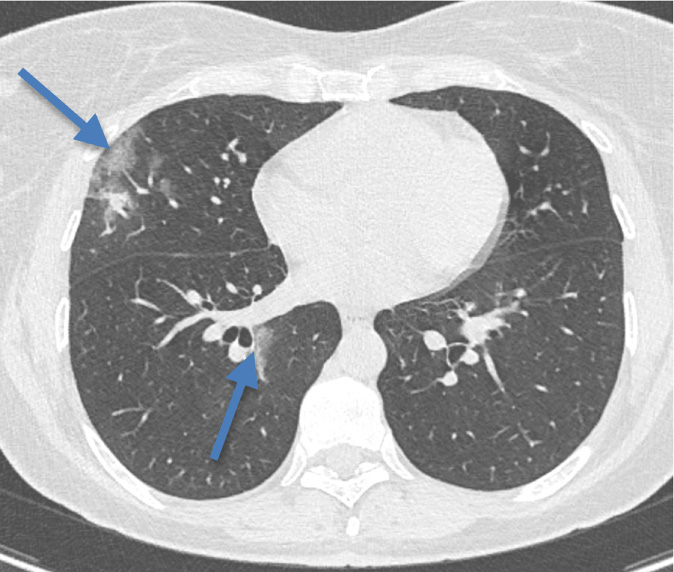

Pneumopathie en rapport avec la COVID-19